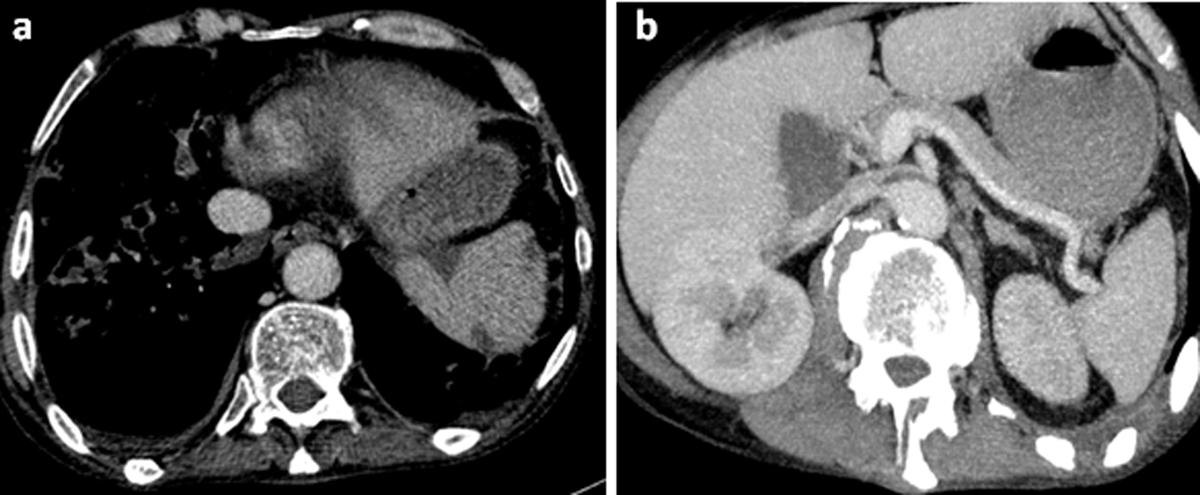

A contrast-enhanced abdominal computed tomography was performed. Axial images of portal phase demonstrated multiple wedge-shaped non-enhancing areas at the periphery of the spleen suggestive of splenic infarcts (Figure 1a). Splenic vein was permeable (Figure 1b). Axial and sagittal images of arterial phase revealed a small splenic artery related to severe stenosis and angulation of celiac axis caused by a thick soft tissue band (5 mm) anterior to the abdominal aorta creating a hooked appearance (Figure 2a, b). Coronal maximum intensity projection CT showed a prominent gastroduodenal artery with large collateral vessels around the pancreatic head (Figure 3). Median arcuate ligament syndrome causing splenic infarcts was retained and the patient was referred to vascular surgery service.

Figure 1